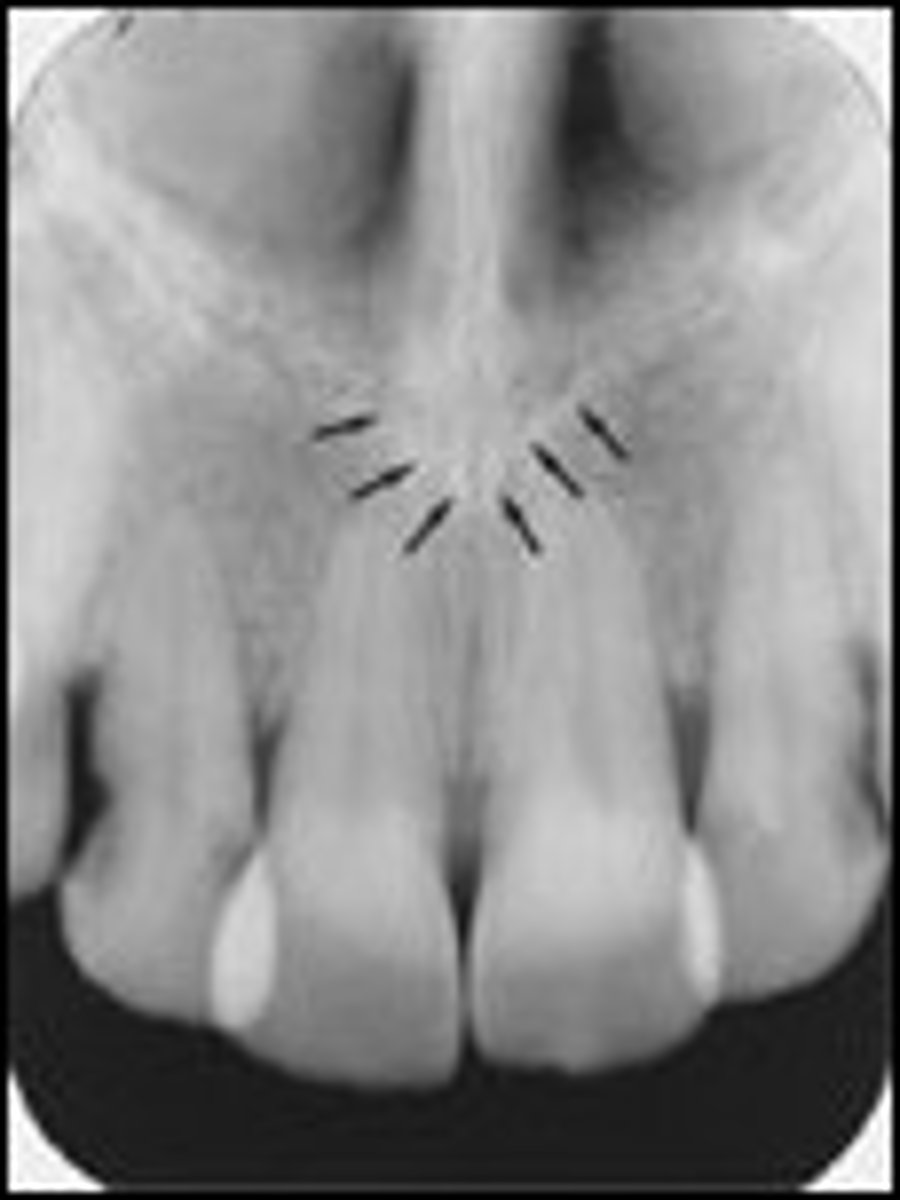

Nutrient canals

What is the radiolucent structure seen here?